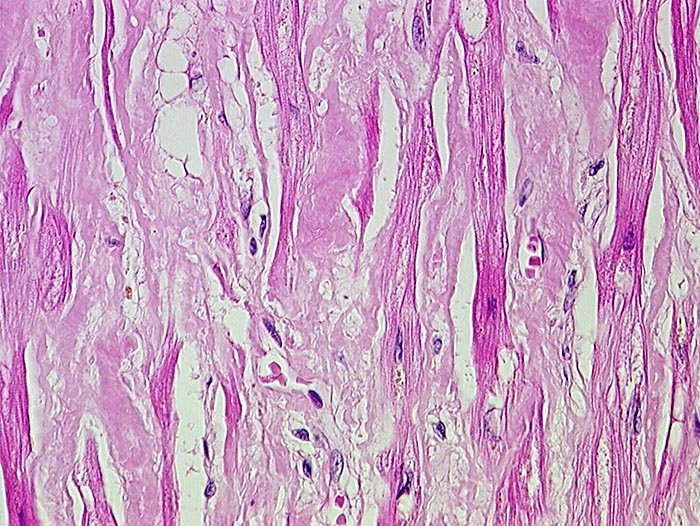

PathoPic ID 532 - AL-Amyloidose

AL-Amyloidose

Systemerkrankung/Immunpathologie

Herz

Kardiovaskuläres System

Interstitielle azelluläre Amyloidablagerungen.

Monoklonale Plasmazelldyskrasie IgG-lambda seit 9 Monaten.

Histologie

67

männlich